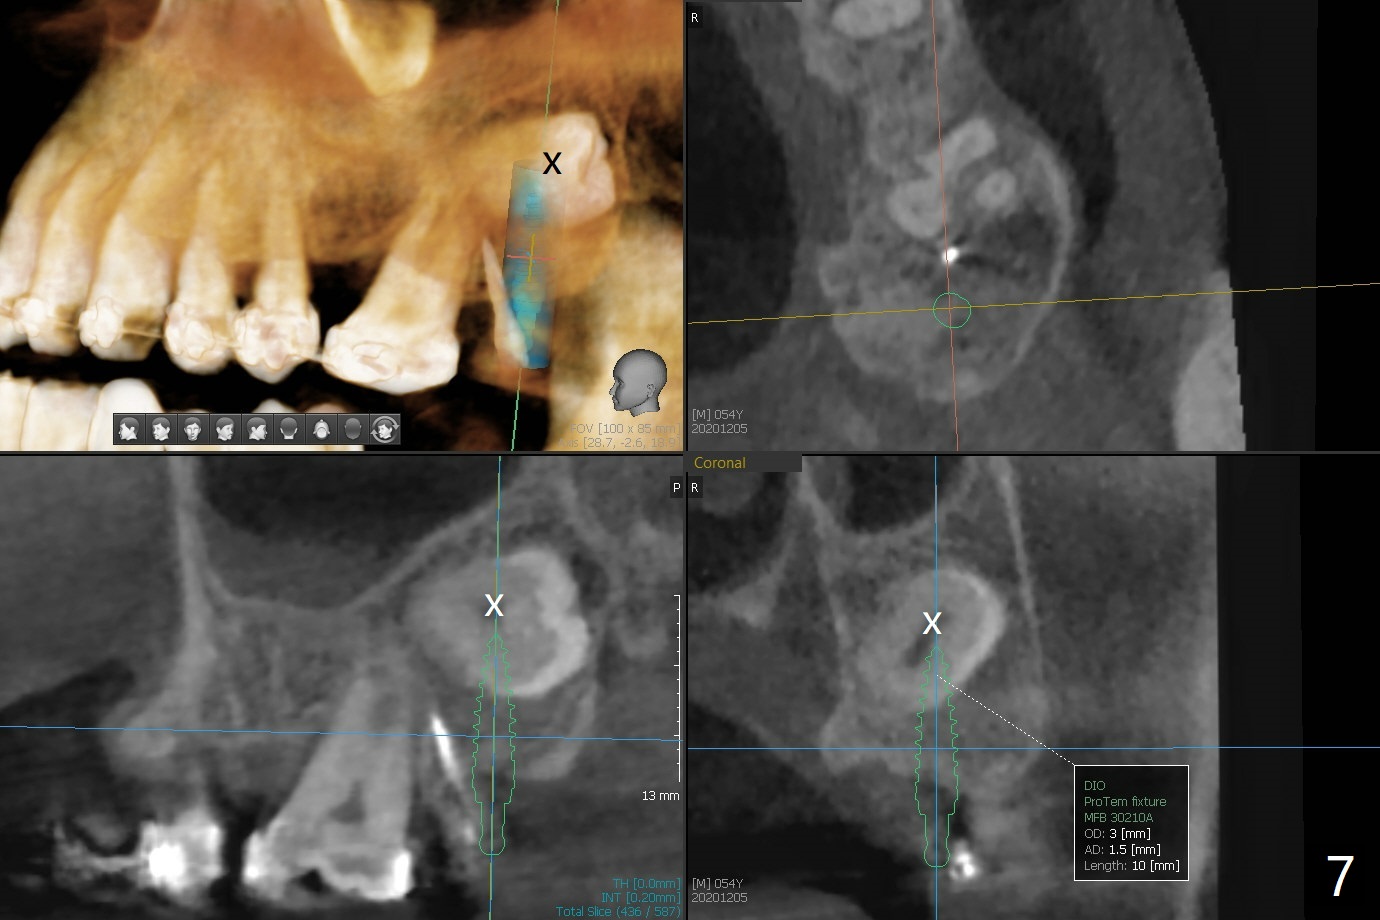

为了在左上6,左下7种植,使用右上3至左上5作为支抗推左上7远中,但是六个月效果不显著(图一),CT显示阻生牙(图一,二:8)没有阻挡。7远中植入1.6x8毫米微型植体,不过接近7根尖(图三),微型植体应该改变角度,而且往远中颊侧移位。最后效果不错(图四),植体马上启用(图五),而且同时取模做左下7导板。在微型植体牵引下,左上7的确往远中移位(图六,与图四对比),但是植体松动,马上植入3x10(2)毫米一段式植体,由于8阻挡,后者没有完全就位,稳定性差,没有启动。几天后也脱落。病人急着完成治疗,因为咀嚼困难。补救方法便是拔除阻生牙9(图七:x),让植体完全就位。切开后发现牙槽嵴处严重骨质吸收缺损(图八:D),离7很近,不适合种植。拔除8后(图九:S(socket)),两处植骨(粘性,图十),覆盖PRF膜,缝合。矫正九个月6空间相当双尖牙(图十二),还想增加2毫米才种植,病人急于完成治疗,所以再次植入微型植体,不同之处是切开,发现7远中颊侧骨质密度低(用探针),因此微型植体在腭侧植入(图十一:P),扭力似乎高,1.6x8毫米植体仿佛植入8牙槽窝(图十二:红虚线)。微型植体牵引一个月,磨牙缺牙间隙大约前磨牙大小,准备在远中(图十三)植入直径小植体(图十四),当后者整合时,用它继续推7。